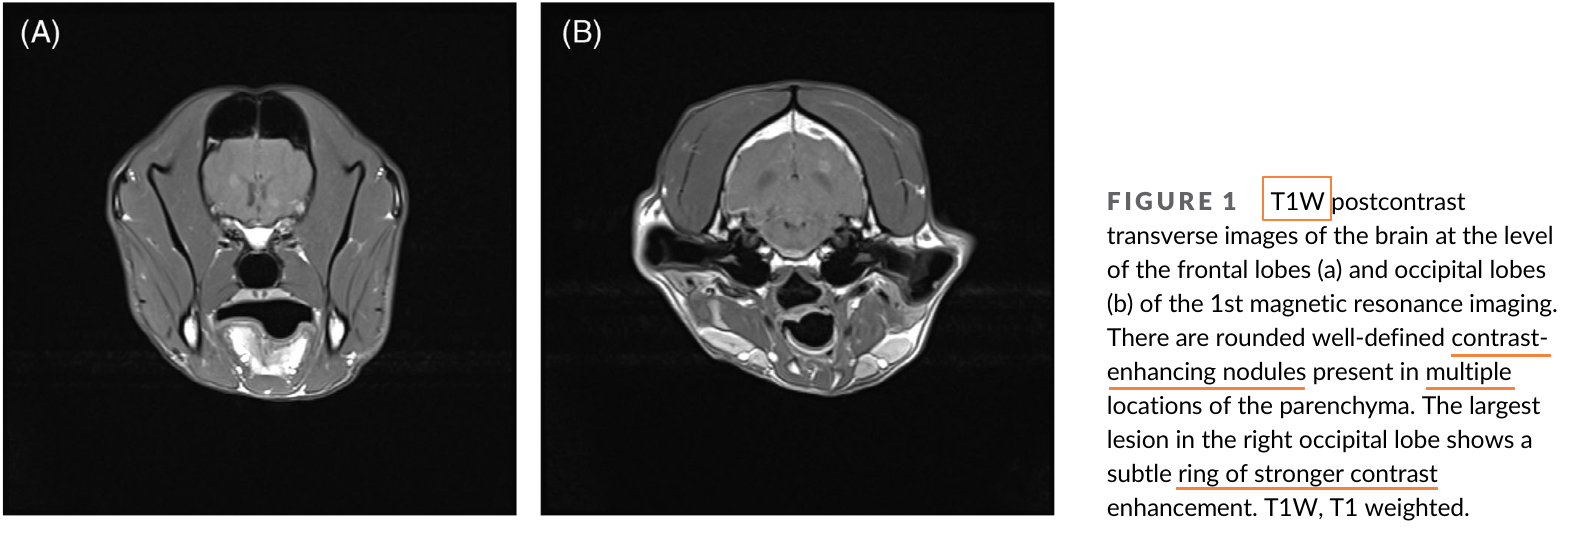

칸디다는 곰팡이성 질환으로 보통 거론되는 게 에이즈 환자등, 면역계가 무너진 환자에서 이차적 기회감염에 해당하는 부분이다. 개에서도 마찬가지로 대부분 면역 억제 치료를 받을 때 주로 증상이 나타날 수 있는데 이번 증례는 뇌에 감염이 있을 때의 증례, 특히 MRI 촬영과 부검을 통한 재확인이 매우 가치 있는 논문이라 하겠다.